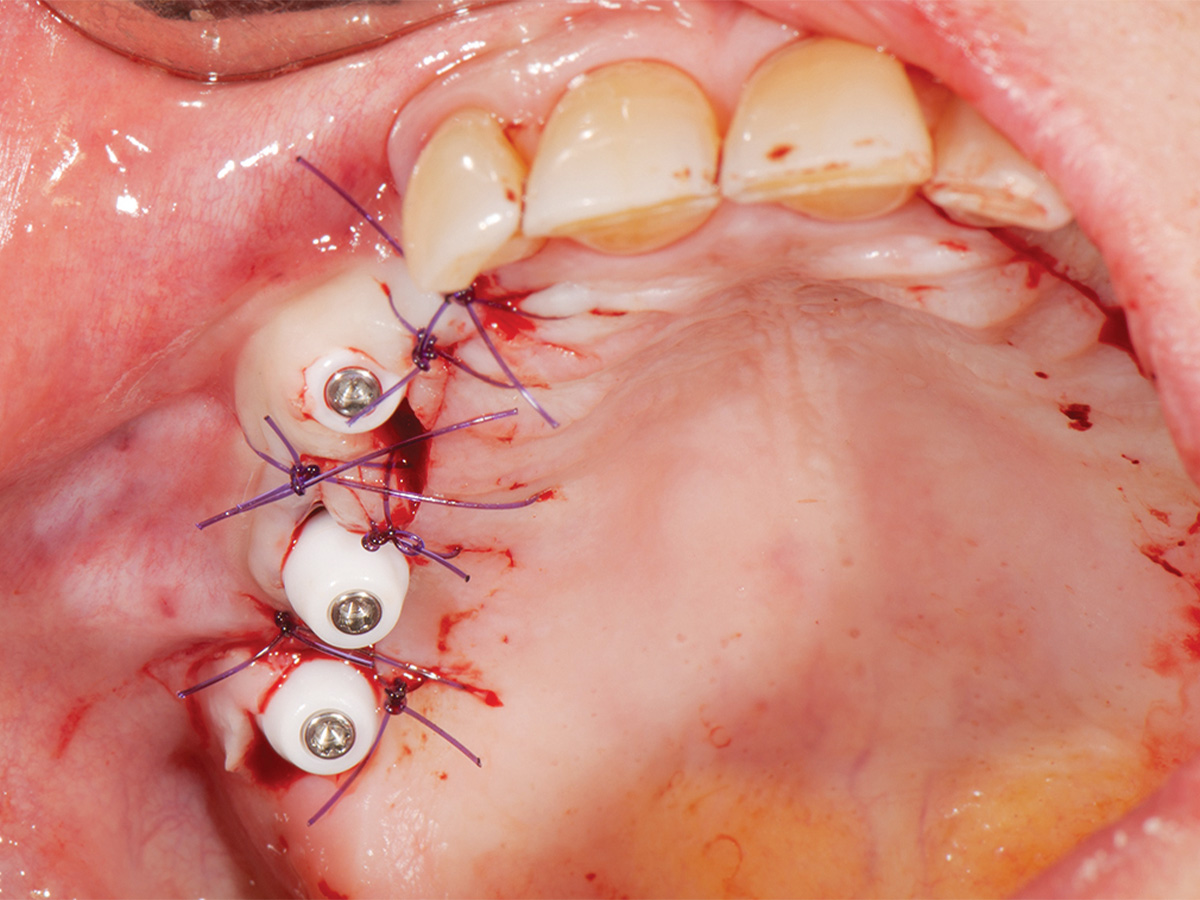

Abbildung 8

Wundverschluss, Okklusalansicht.